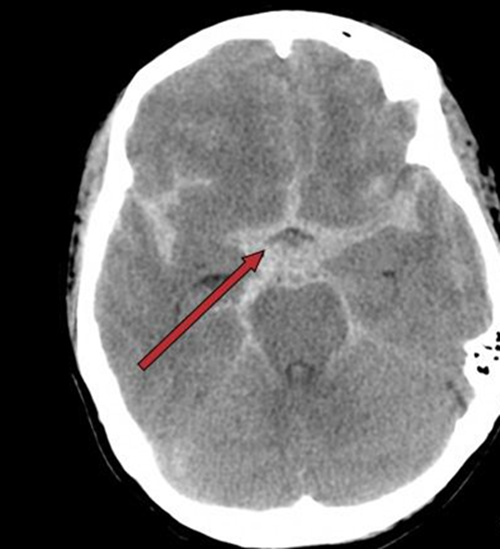

送进医院的时候,患者的病情已经相当严重,她两侧的瞳孔已经不等大,而且对光反射很弱!立刻完善了头颅CT等检查,结果却是蛛网膜下腔出血!